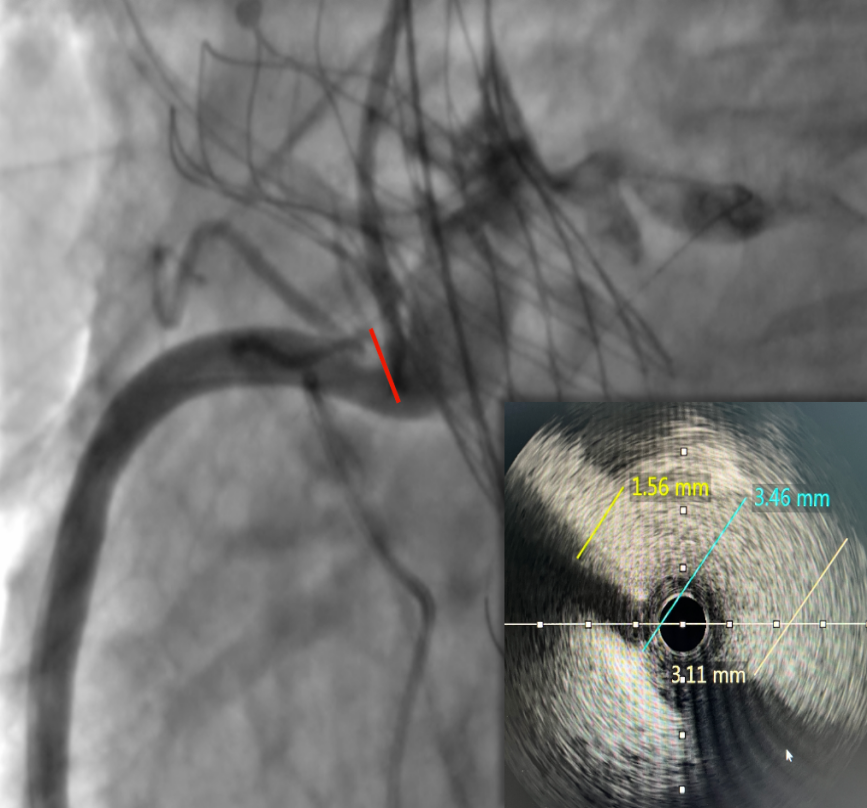

左冠口疑似遮挡

IVUS检查冠脉开口,

进一步精准评估冠脉开口遮挡情况

IVUS检查提示因原瓣叶遮挡,左冠开口受阻,最窄处残余缝隙0.66-0.82mm。

右冠开口残余1.56mm-3.46mm,血流无明显阻挡。